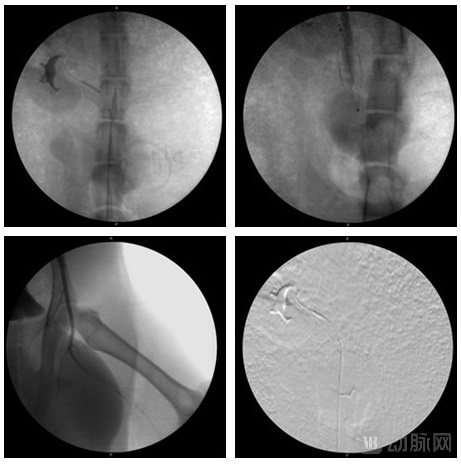

2023年6月26日,北京圣安杰医疗科技有限公司(以下简称“圣安杰医疗”)自主研发的神经外周血管介入通路机器人成功完成首次动物实验。

此次实验由首都医科大学宣武医院血管外科谷涌泉教授等多位临床专家与圣安杰医疗团队共同完成,实现了远程操作下的全流程支架/球囊/滤器植入术,其中滤器置放由机器半自主运行。本次实验验证了圣安杰医疗血管介入机器人的安全性、有效性和精准性。各项实验结果均达到预期目标。

圣安杰医疗创始人狄亮告诉动脉网:“全球范围的血管介入机器人多在PCI领域以快速交换路径设计为出发点,能在外周和神经血管介入领域,进行可控弯操作并实现半自动操作的机器人尚未出现。但是我们的机器人已在本次动物实验中成功验证了这两项核心技术。”